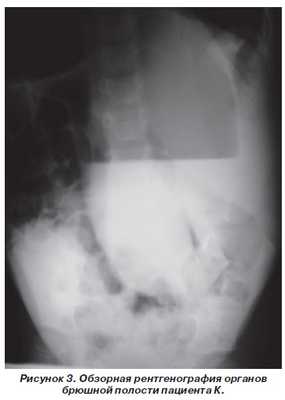

Произведена обзорная рентгенография брюшной полости, был выявлен гиперпневматоз тонкой и толстой кишки. Просвет толстой кишки расширен до 11 см с горизонтальным уровнем в мезогастрии справа. Под правым куполом диафрагмы газ в петле толстой кишки. Печень смещена книзу и медиально, ее верхний край на уровне Th11 (рис. 3).

При ирригоскопии от 31.03.09 г. контрастом выполнилась левая половина толстой кишки. Дальше контраст не проник. Участков аганглиоза нет (рис. 4).